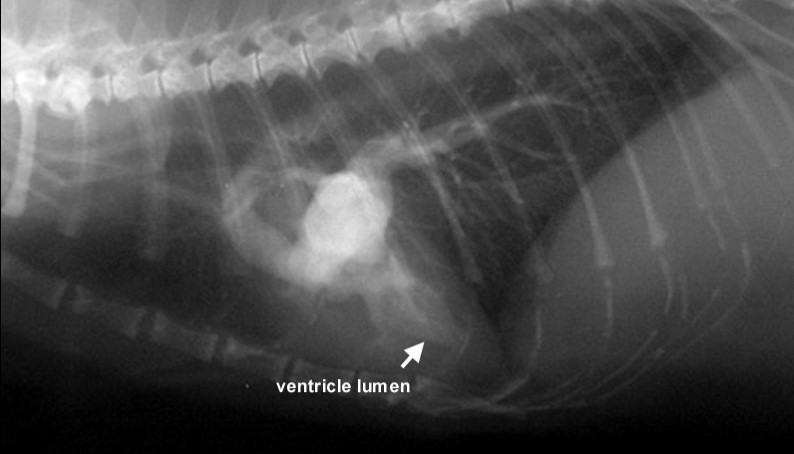

• Genetic diseases. They are the most common causes of cardiomyopathy. Studies by British scientists in 2017 showed that cardiomyopathy affects about 10% of Burmese cats. The most common is hypertrophic cardiomyopathy, which affects almost 7% of this breed.